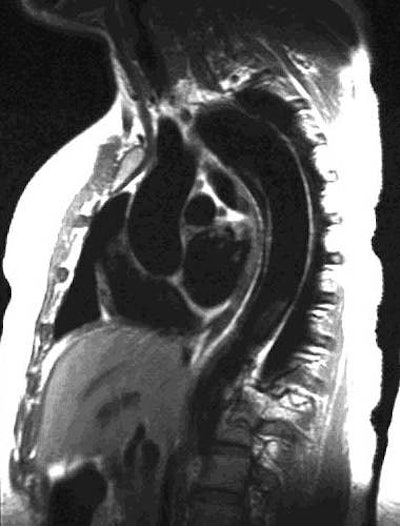

Oblique sagittal SE images showing the flap originate adjacent to the origin of the left subclavian artery and

extending down into the abdomen: